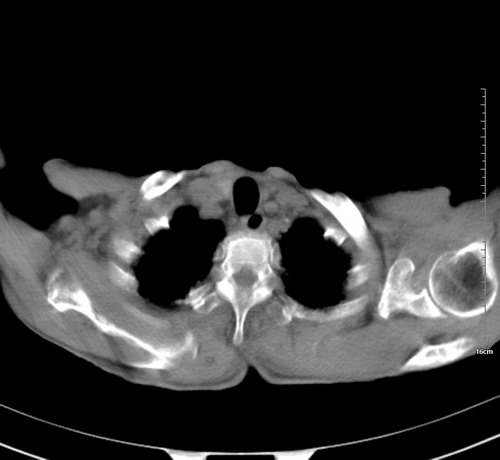

中后纵隔占位,气管、食道受压、变形、移位。恶性可能性大。

考虑:中后纵隔转移瘤可能性大,主动脉硬化。

中后纵隔占位, 考虑:转移瘤不除外.

1 气管旁、隆突下淋巴结明显肿大,肝左叶外侧段低密影,都考虑转移。

纵隔淋巴结肿大,考虑转移而来

后中纵隔团块影,伴气管、食道受压移位,首先考虑转移瘤,肝s5段低密度灶。建议增强检查,另外其结肠是否有问题请提供,右肺部分肺叶局限含气增多,考虑局限肺气肿。

建议强化检查,考虑纵隔型肺癌,小细胞可能性大。

后中纵隔淋巴结肿大,首先考虑转移瘤。